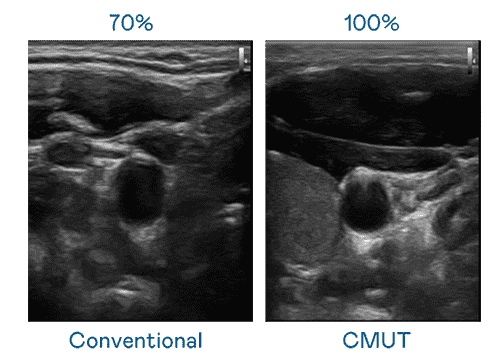

CMUT 技术是一种用电容式微机电元件来产生超音波讯号的技术。。。。与传统 PZT 压电式技术相比,,,,CMUT 频宽增加 30%,,更宽频的超音波讯号让影像解析度大幅提升,,,是实现高影像品质医疗超音波扫描、、、、促进精准医疗发展的关键技术。。。。

大频宽带来超清晰影像

超音波影像的解析度高低,,,首先取决于探头能发出的讯号频宽。。。。z6尊龙 CMUT 可提供高清晰的超音波讯号,,,提供高频宽、、、、高灵敏度、、、、影像纹理细节更高的超音波影像,,协助医护人员缩短影像判读时间及利用精准的医疗影像进行诊断。。